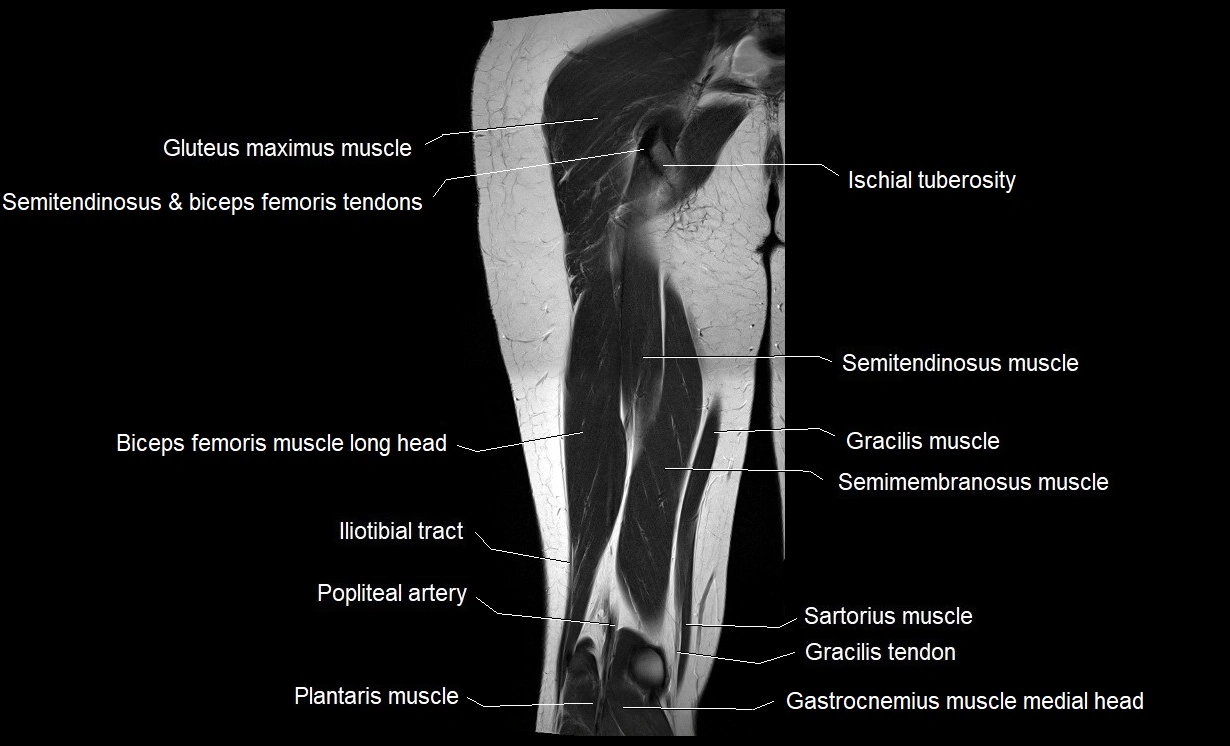

- Biceps femoris muscle (Long head)

- Gluteus maximus muscle

- Gracilis muscle

- Iliotibial tract

- Plantaris muscle

- Popliteal artery

- Sartorius muscle

- Semimembranosus muscle

- Semitendinosus muscle